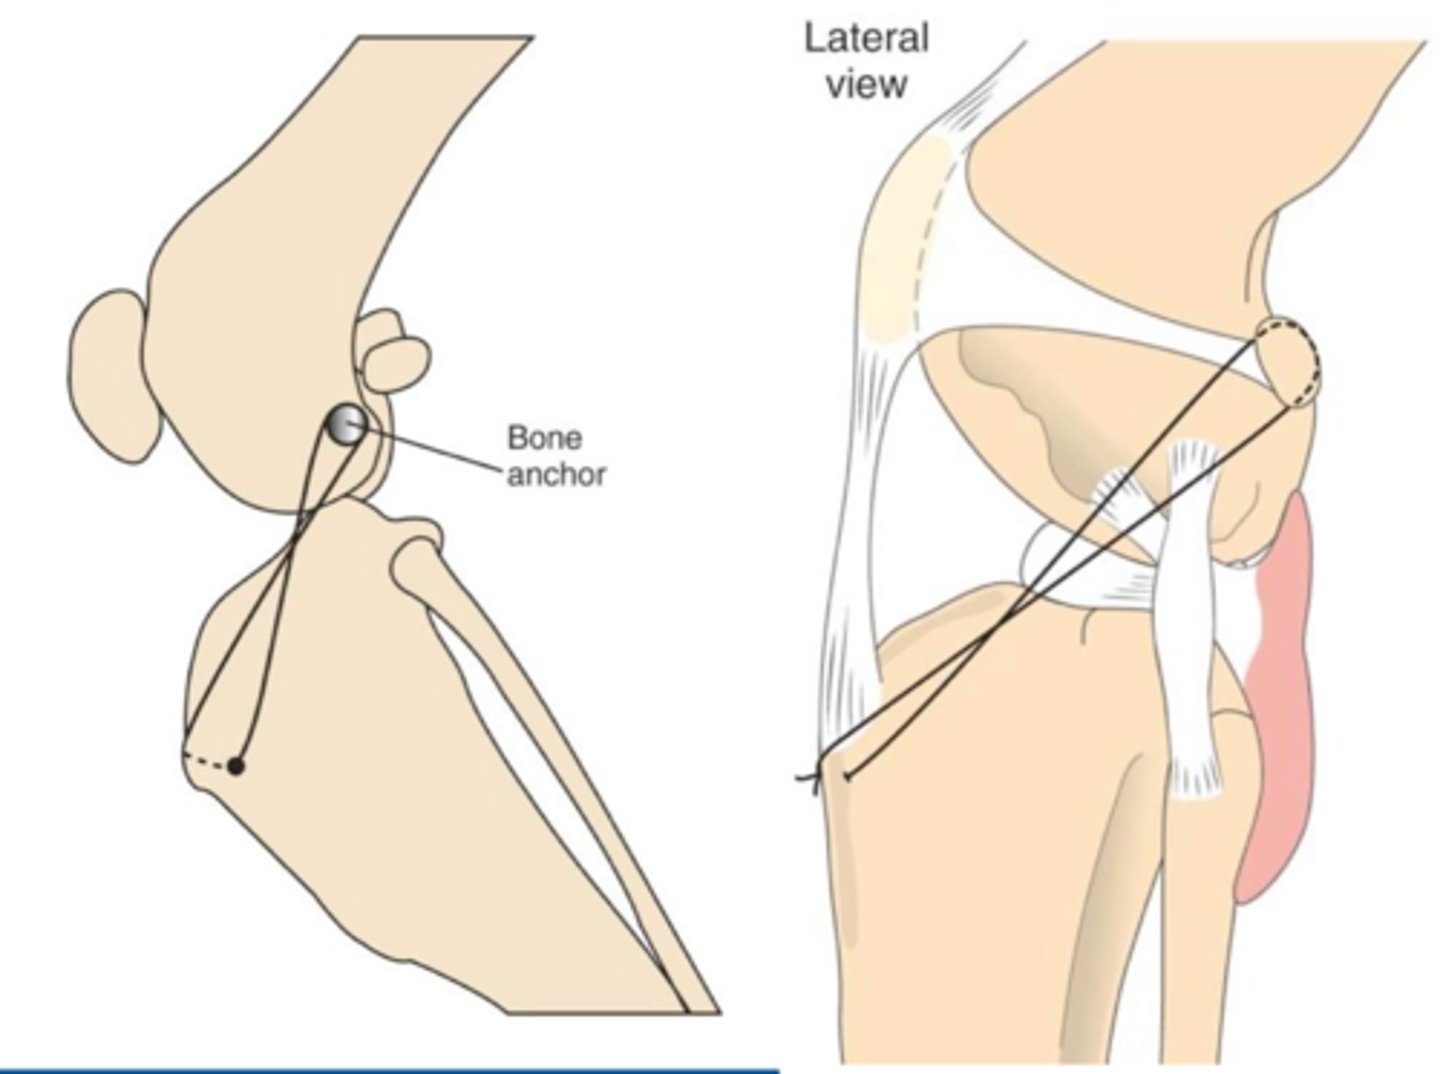

tightrope stabilization

what procedure is shown here